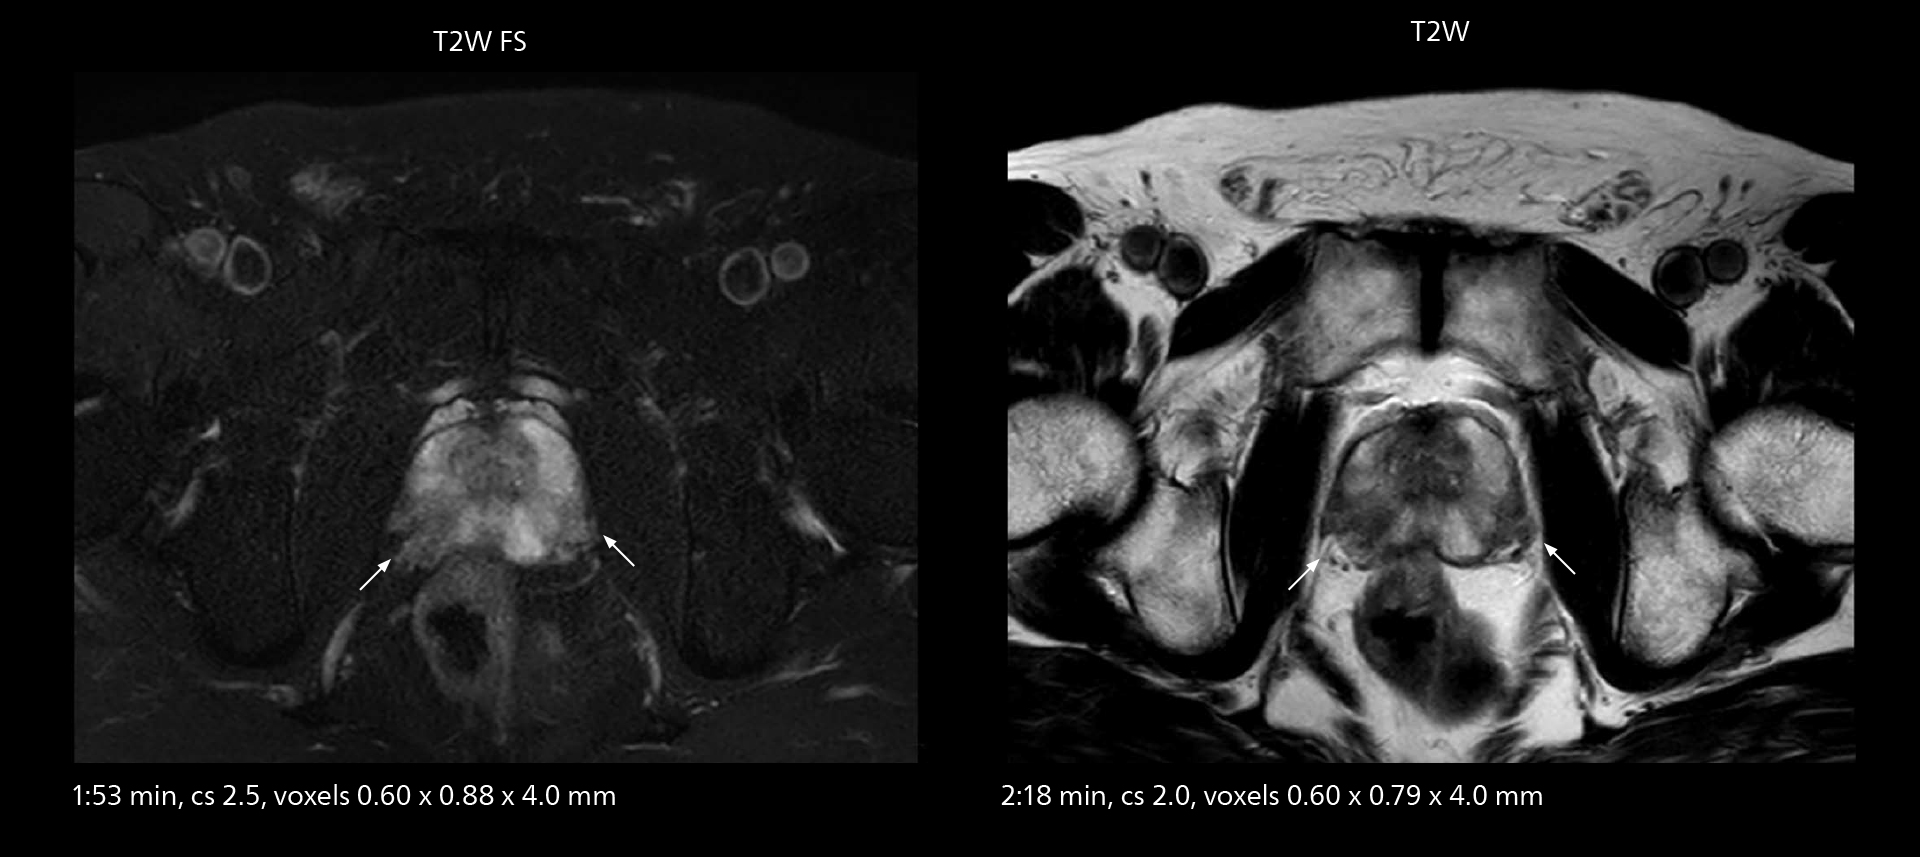

MRI of prostate

Examples of prostate imaging showing faster scan times and improved resolution illustrate the power of SmartPath to Elition X in this case of prostate cancer with PI-RADS score 4.

MRI of prostate

Examples of prostate imaging showing faster scan times and improved resolution illustrate the power of SmartPath to Elition X in this case of prostate cancer with PI-RADS score 4.